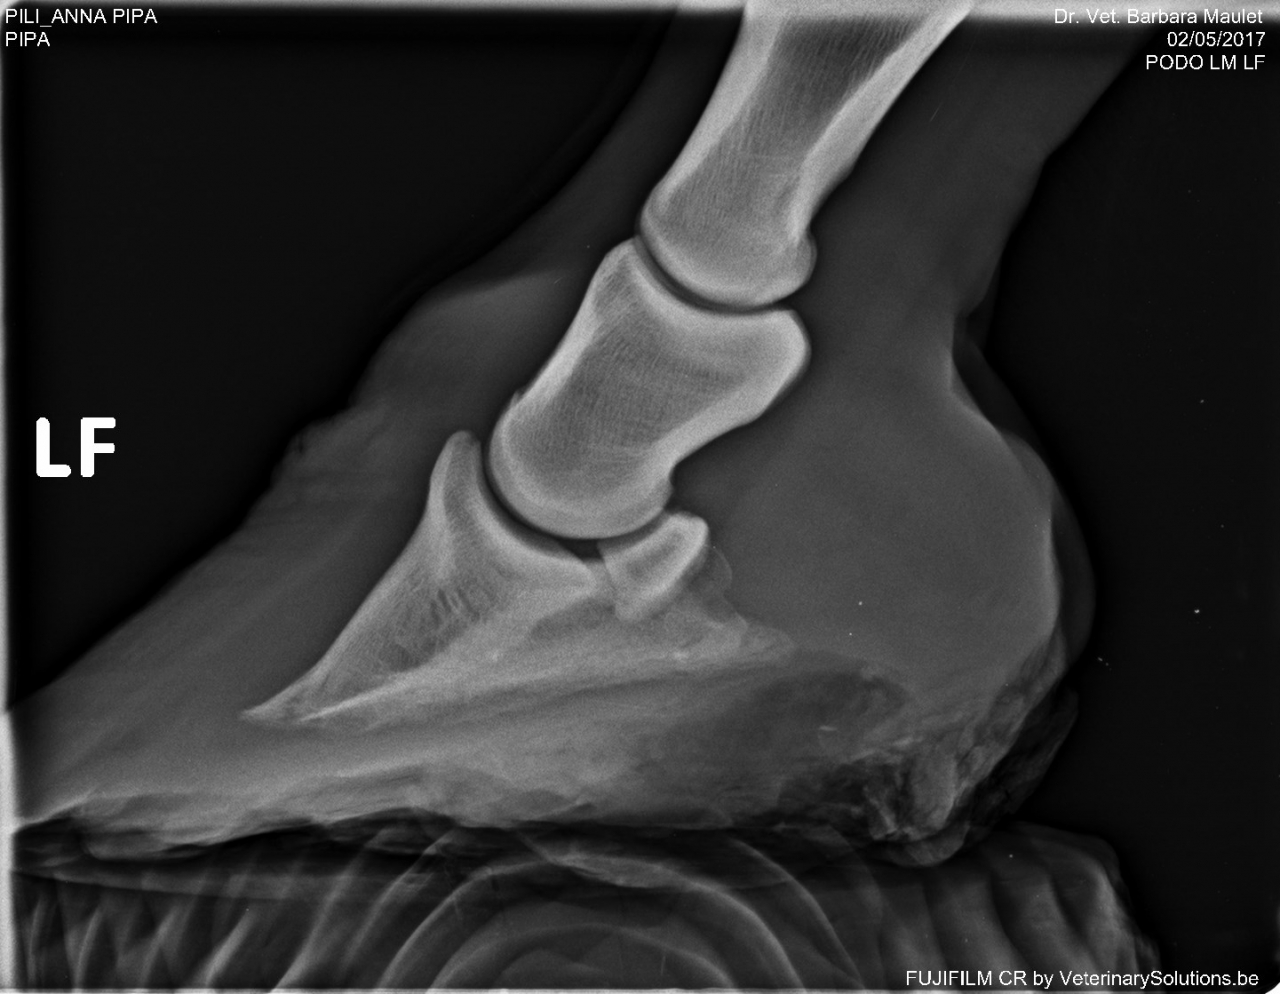

DéconnectéDire merci | j'ai fait piquer mardi la petite fourbue juste après avoir vu ses radios pour mémoire la photo: ![]() à des fins didactiques les radios ![]() ![]() non seulement il y a bascule totale de la phalange mais un gros remodelage de l'os, y avait rien à récupérer. Pipa la jument de manège a aussi été fourbue plusieurs fois, elle ne marche pas correctement des 2 antérieurs. son taux d'ACTH est à 96 ce qui ne me semble pas énorme. Les radios: ![]() ![]() basculement présent mais nettement moins important, léger remodelage. Rassurez vous le MF est passé hier ... |

| Dire merci | Les radios font froid dans le dos 😔 Bon voyage à cette petite 🌈 |

| Dire merci | les radios de la petite fourbue ![]() Elle aura au moins connu un peu de réconfort dans sa fin de vie et aura évité de longues semaines (mois, années ?) de souffrance supplémentaires |